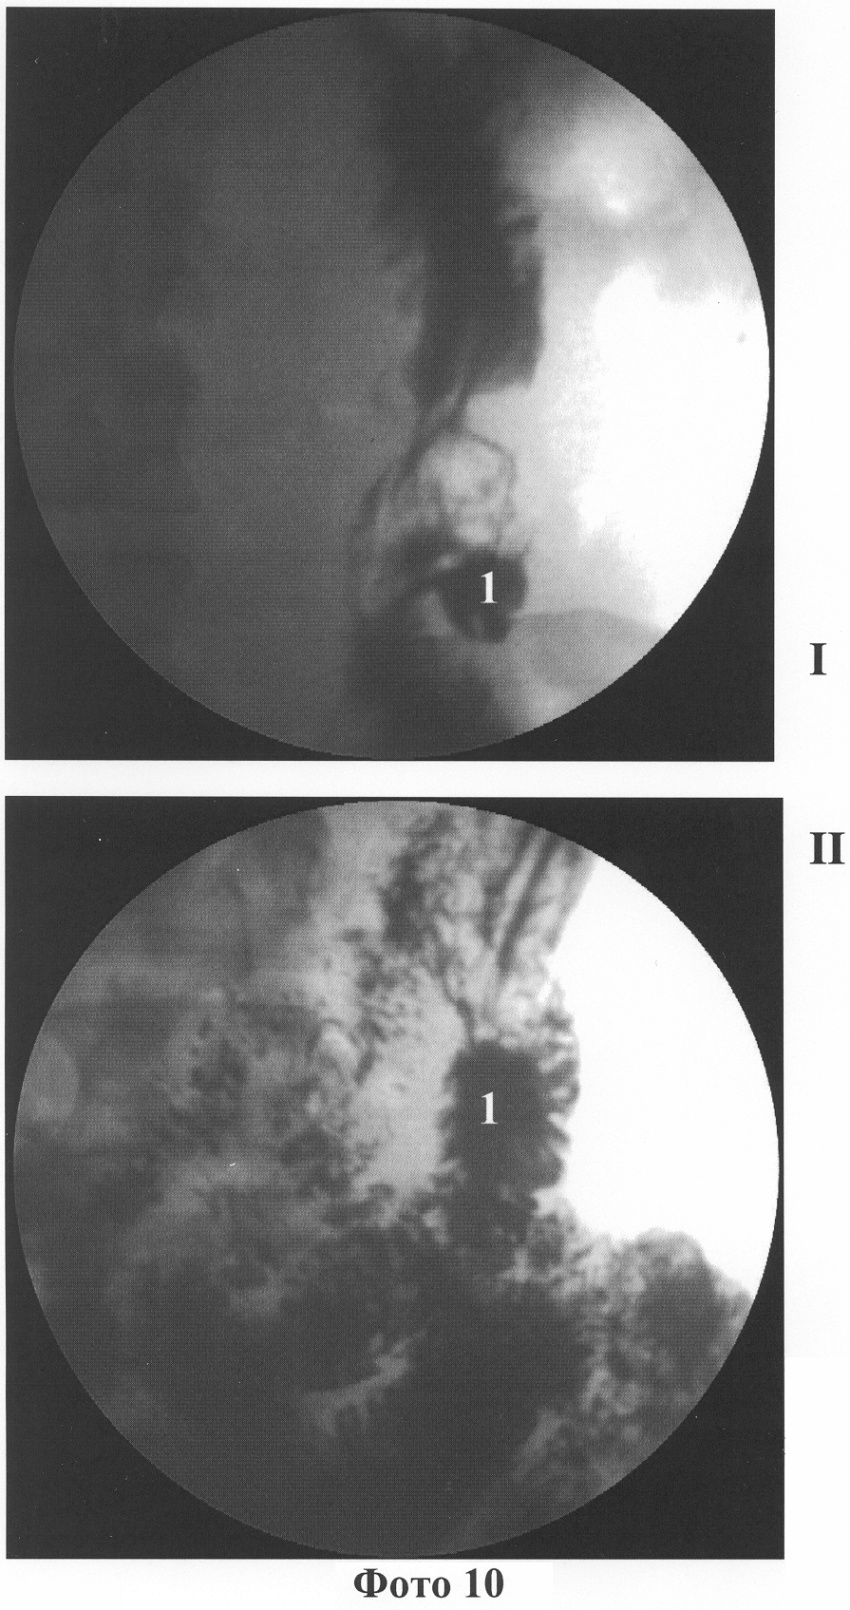

ФГДС с прокрашиванием (краситель – 0,5% раствор метиленовой сини): В области ГЭА язва размерами 0,6×0,8 мм (расположена на “шпоре”), в начальном отделе отводящей петли ГЭА выявлена пептическая язва размерами 0,5×0,4 см, отмечен рефлюкс кишечного содержимого в культю желудка. Заключение: Состояние после резекции желудка по Бильрот-II. Анастомозит. Пептическая язва ГЭА, пептическая язва начального отдела отводящей петли ГЭА. Поверхностный гастрит. Дуоденогастральный рефлюкс (приложение 9, 1 – пептическая язва ГЭА, 2 – лигатурная нить, 3 – околоязвенный воспалительный валик, 4 – воспалительный валик (увеличение), 5 – гипертрофия слизистой оболочки воспалительного валика, 7 – пептическая язва начального отдела отводящей петли).

Заключение: Состояние после резекции желудка по Бильрот II, пептическая язва ГЭА, начального отдела отводящей петли. Гастрит культи. Анастомозит. Нефиксированная аксиальная грыжа пищеводного отверстия ДПК. ДГР. (Приложение фото 10, I – в положении стоя, II – в положении лежа, 1 – стойкое депо бария “ниша” в области гастроэнтероанастомоза).